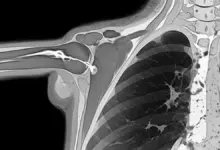

A sigla vem do inglês Humeral Avulsion of the Glenohumeral Ligament, que descreve um descolamento do ligamento glenoumeral (geralmente o inferior) na sua inserção no úmero.

O ombro é a articulação mais móvel do corpo, com grande liberdade de movimento e, por isso, depende de estabilizadores dinâmicos (músculos) e estáticos (ligamentos, cápsula e labrum).

Na lesão HAGL, ocorre um “arrancamento” da cápsula/ligamento na parte umeral.